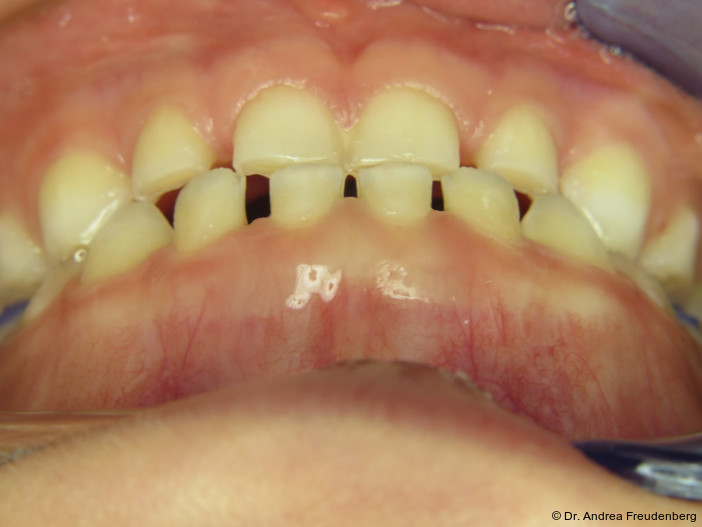

Da Pathologie, d.h. Fehlwachstum, allgegenwärtig ist, möchten wir kurz die physiologische Gebissentwicklung ins Gedächtnis zurückrufen. Ein physiologisches Milchgebiss sollte

- eine halbrunde Form der Zahnbögen,

- eine dezente sagittale und vertikale Frontzahnstufe und

- im Alter von vier bis fünf Jahren Lücken zwischen den Milchschneidezähnen aufweisen (die bleibenden Frontzähne sind ca. ein Drittel breiter als die Milchzähne).